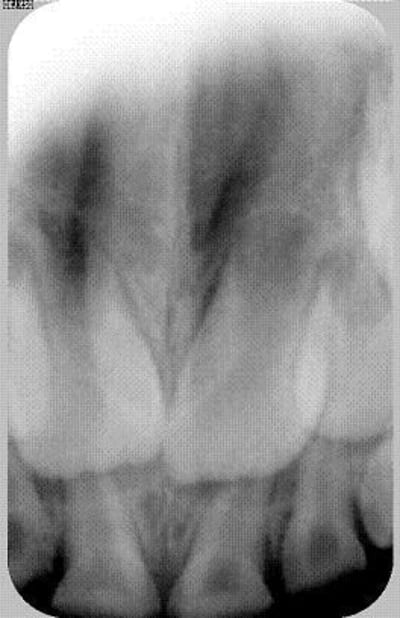

petit bout de chou tout mignon tout gentil mais tout un cinoche pour faire des photos...

pas manqué de biberon sucré visiblement

5ans....pfff...par quoi on commence...

t'as pas une pano ou des radios postérieures ?

si derrière y a assez de dentine saine, tu peux parfaitement faire des coiffes pédos ajustées et scellées au verre inomère, ça marche très bien.

pour le haut devant il faut enlever. le gamin ayant 5 ans, ça va repousser rapidement..

bas même topo.

rien de bien compliqué, reste juste à être payé du boulot, parce que là y en a pas mal.

14 dents a traiter a 5 ans et des parents criminels a eduquer( freres et soeurs?),normal que tu te sentes un peu depasse

Si tu decides quand meme de soigner le bout de chou,une pano aiderait a determiner le temps qu'il te reste avant l'arrivee des 6 dans cet environnement hostile

coiffes pedo au fond (mais avant, pulpo? canaux?)

devant, les extraire? (la radio montrent quand meme des racines lactéalas completes encore)ou pulpo itou mais comment reconstruire? coller au verre ionomere sans chercher a remonter les formes?